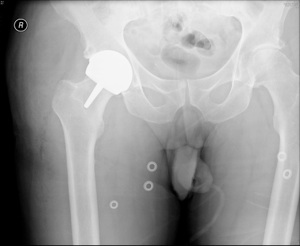

hip resurfacing

The first hip resurfacing was implanted in 1991. It was designed for younger more active patients by Mr Derek McMinn at the Royal Orthopaedic Hospital, Birmingham. It is a more complex procedure compared to a routine hip replacement and should be performed by a specialist hip surgeon. It involves replacing the ball of the hip joint without placing a long stem down the centre of the femur ( like a traditional hip replacement).

A small number of patients can have problems with high levels of metal ions in the tissues which may cause failure of the resurfacing. This has been highlighted recently in the media with concerns regarding the particularly high failure rate of the ASR hip resurfacing component. Research has shown that the brand, size, and sex of the patient together with position of the implant may affect the amount of metal ion production. Correct positioning is paramount, and for this reason Mr Higgins feels that computer aided navigation is a valuable tool.